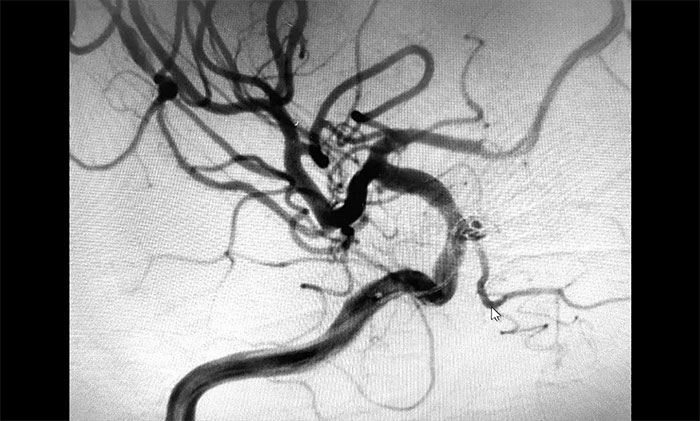

考虑脑出血后遗症可能,于耀宇主任为秦女士完善相关检查。通过DSA全脑血管造影检查,发现患者右侧颈内动脉眼动脉段动脉瘤形成,瘤囊直径约3mm,就像一颗长在动脉血管上的“葡萄”,里面充盈流淌着血液。

▲ DSA检查发现颅内动脉瘤

于主任介绍,眼动脉是眼眶及内容物最主要的血液供应,是颈内动脉主要分枝,也是交通颅内外血管的重要通道。该处是颈内动脉进入颅骨后的第一个主要分支,如果患者血管壁先天发育缺陷或有高血压等情况,在血流冲击下,容易形成动脉瘤。